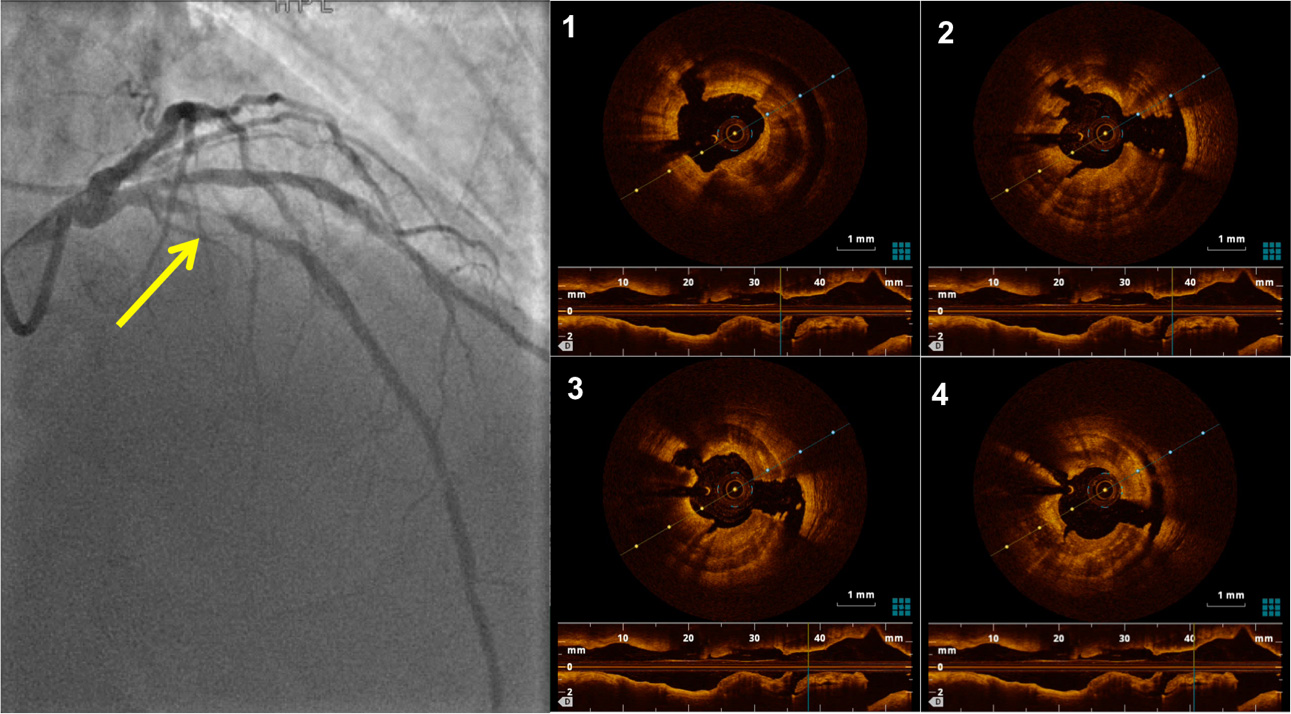

Figure 1. Left panel: Left coronary angiogram showing severe concentric stenosis in the proximal LAD (yellow arrow). Right panel: OCT images of a severely calcific concentric plaque, presenting deep radial and longitudinal (long-axis view shown below) fractures after combined treatment with Rotational Atherectomy (Rotablator) and IntraVascular Lithotripsy (Shockwave). LAD: Left anterior descending artery, OCT: optical coherence tomography.